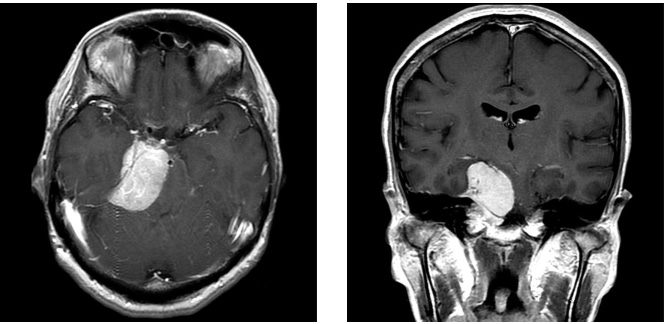

症例3

症例3は42歳女性。意識消失にて発症。CT、MRIにて内頸動脈、中大脳動脈を巻き込む大型の前床突起部起源の髄膜腫を認める。

中大脳動脈の血流が低く、血管損傷を来す可能性もあるので、浅側頭動脈-中大脳動脈バイパスをおいた後に腫瘍内より血管を掘り起こすように摘出を行った。

細い脳深部に至る血管も保護して摘出した。術後四肢麻痺等なく回復。

術前画像:内頸動脈などの血管を巻き込み狭窄する(反対側と比較)腫瘍をみとめ周囲に脳の腫れを認める。

術後画像:腫瘍はほぼ摘出され、脳梗塞等の合併症は認めない。